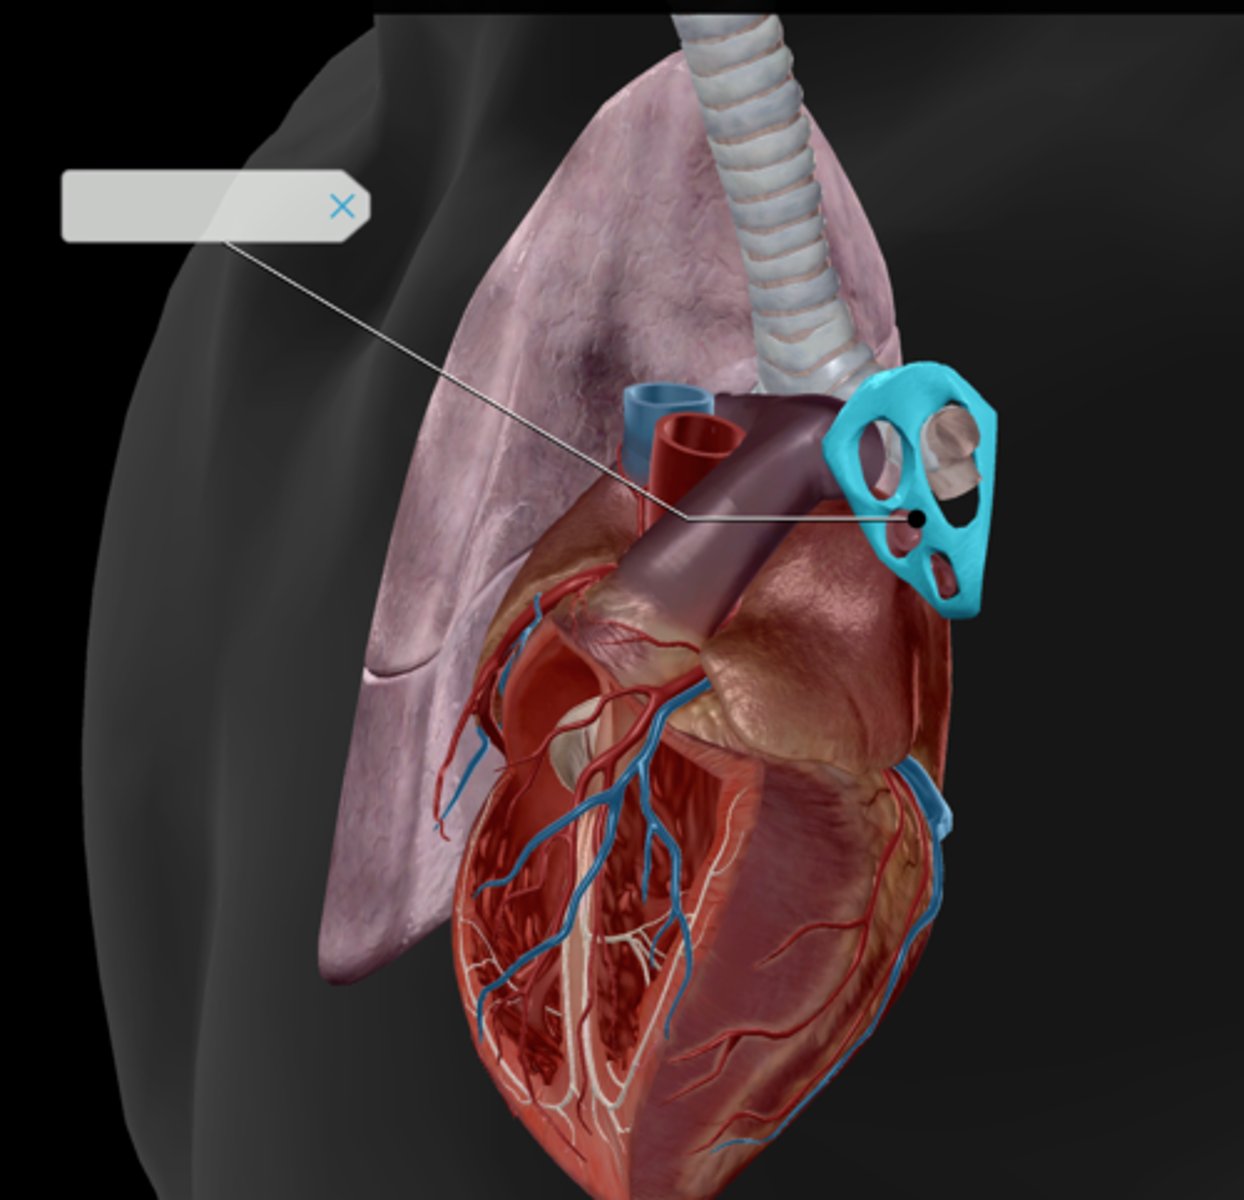

Hilum

Superior lobe

Middle lobe

Inferior lobe

Horizontal fissure

Oblique fissure

Pulmonary arteries

Pulmonary veins

Pulmonary trunk

Diaphragm